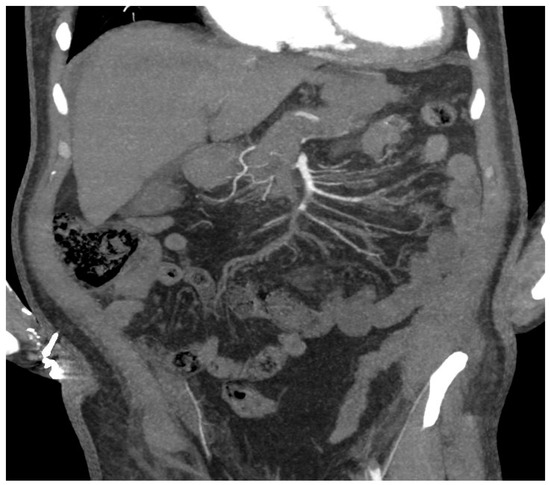

- In one case (9.1%), hypoperfusion of the intestinal loops was evidenced due to extensive thrombosis of the superior mesenteric artery (Figure 5); this patient was the one with predominant abdominal pain symptoms.